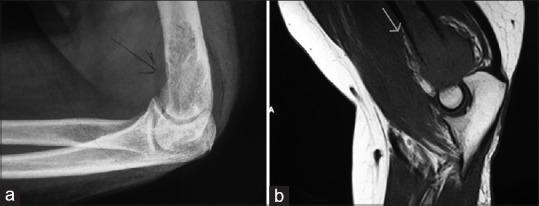

Isolated skeletal metastasis in endometrial carcinoma at recurrence is very rare. We report a 52-year-old woman diagnosed to have FIGO Stage 1b, Grade 1 endometrioid adenocarcinoma, presenting with isolated distal humerus metastasis, 2 years after surgery and adjuvant radiotherapy for primary disease. Imaging, bone scintigraphy, and cytology confirmed the diagnosis of poorly differentiated metastatic adenocarcinoma. She was treated with local radiotherapy followed by six cycles of paclitaxel and carboplatin chemotherapy along with zoledronic acid, monthly. She is symptom-free after the treatment and at a first follow-up visit after 3 months.

子宫内膜癌复发时出现孤立性骨转移非常罕见。我们报告一名52岁女性,诊断为FIGO 1b期、1级子宫内膜样腺癌,在原发性疾病接受手术和辅助放疗2年后,出现孤立性肱骨远端转移。影像学检查、骨闪烁显像和细胞学检查确诊为低分化转移性腺癌。她接受了局部放疗,随后接受了六个周期的紫杉醇和卡铂化疗,并每月使用唑来膦酸。治疗后她无症状,在3个月后的首次随访中情况良好。